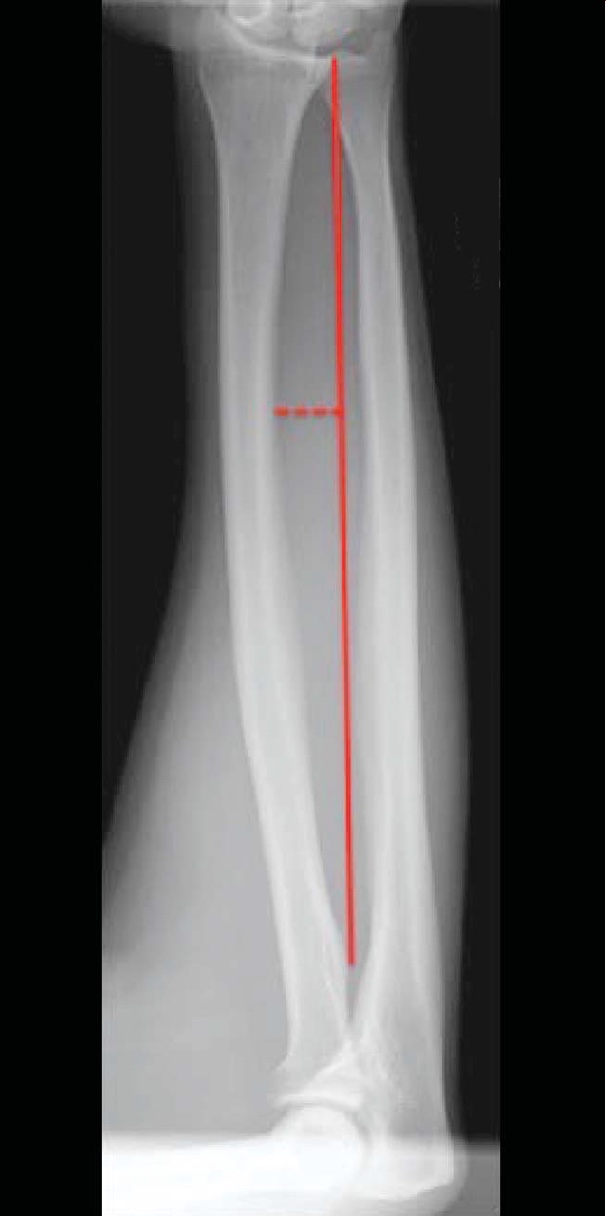

Radius and Ulnar Shaft Fractures